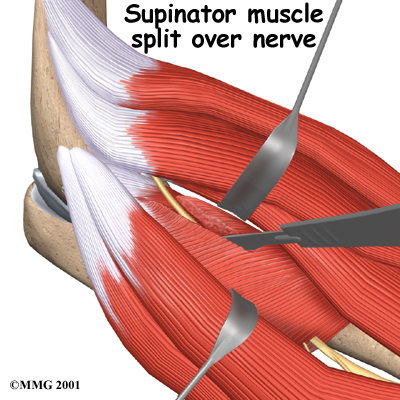

The goal of surgery for radial tunnel syndrome is to relieve any abnormal pressure on the nerve where it passes through the radial tunnel. The surgeon begins by making an incision along the outside of the elbow and down the forearm, near the spot where the radial nerve goes under the supinator muscle.

Soft tissues are gently moved aside so the surgeon can check the places where the radial nerve may be getting squeezed within the radial tunnel. The nerve can be pinched in many spots, so it is important to check all the areas that may be causing problems. Any parts of the tunnel that are pinching the nerve are cut. This expands the tunnel and relieves pressure on the nerve. At the end of the procedure, the skin is stitched together.

The following images show each step: